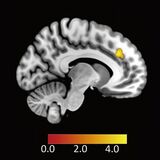

ヒトが不公平な提案を受け入れる時の脳内メカニズムを解明

脳の背側前帯状皮質が「不公平への感情」を抑える2026年2月9日国立研究開発法人情報通信研究機構(NICT)ポイント ■ 交渉の…